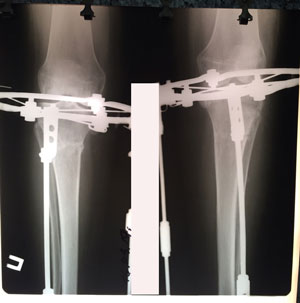

в процессе исправления деформации

IMG_4585-03-08-19-10-15.JPG